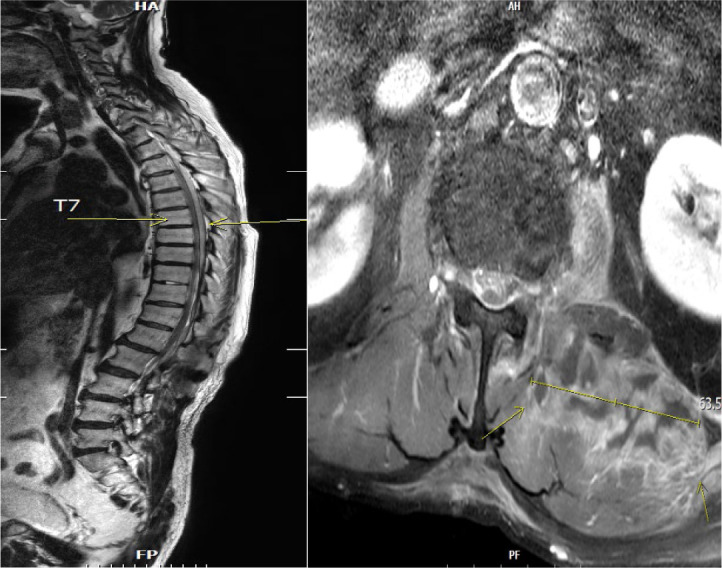

Septic embolism and stroke are serious complications in patients with sepsis and often necessitate urgent surgical intervention to control the source of infection. A 69-year-old man presented with severe pain in his back and left thigh. MRI revealed extensive posterior epidural or subdural abscesses extending from the cervical to the lumbar level, as well as an abscess in the iliopsoas muscle. The patient underwent urgent drainage of the abscesses and decompression of the lumbar spine. Postoperatively, he developed sudden-onset atrial fibrillation and altered mental status. Brain CT showed multiple embolic infarctions. His condition deteriorated due to persistent infection, leading to disseminated intravascular coagulation, acute kidney injury, and septic shock. This case highlights the risk of cerebral embolism and hemorrhagic complications in patients with sepsis who undergo surgery. Early recognition of individuals at high risk and comprehensive perioperative management are critical to reducing the likelihood of such complications.